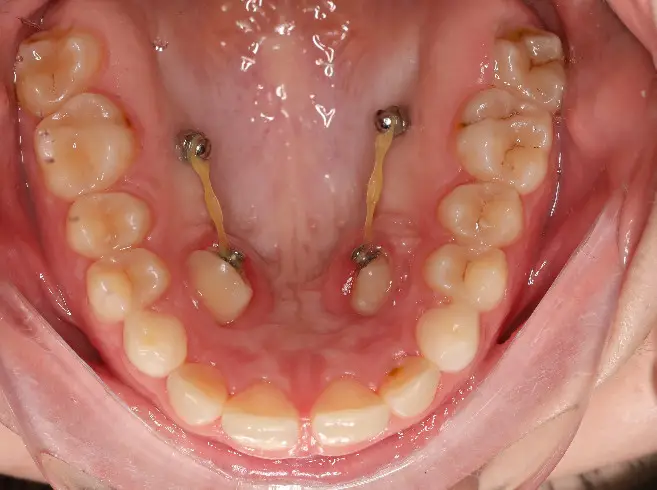

A fogszabályozás során használt mini/mikro implantátumok, mini csavarok segítségével elkerülhetőek a nemkívánatos fogmozgások, akár az állcsonti műtétek is, valamint lerövidíthető a rögzített fogszabályozó készülék viselésének időtartama. Nevüket onnan kapták, hogy méretük töredéke a hagyományos, esztétikai fogászati implantátumoknak, hiszen ezeket a fogíven kívülre, a foggyökerek közötti igen szűk helyekre (vagy esetenként a szájpadba) ültetik be.

A fogaktól független fix támasztékként szolgálnak, így elkerülhető, hogy adott fogak mozgatásakor az azokkal szemben álló fogak is mozgást végezzenek az ellentétes irányba. Az implantátumok titán ötvözetből készülnek, ezért nem csontosodnak be, és könnyedén eltávolíthatóak. Behelyezésük minimális érzéstelenítés mellett, csavaró mozdulatokkal történik, nem igényel vágást, varrást vagy más hasonló beavatkozást.

Néhány nap alatt  teljesen megszokhatóak, tartós fájdalmat nem okoznak.  A rendszeres és alapos tisztításuk azonban elengedhetetlen a viselés ideje alatt, ha el akarjuk kerülni a komplikációkat! Nem megfelelő szájhigiénia mellett ugyanis ínygyulladás alakulhat ki, amelynek következtében az implantátumok hamar elveszíthetik stabilitásukat, és cseréjükre, újbóli beültetésre lehet szükség.